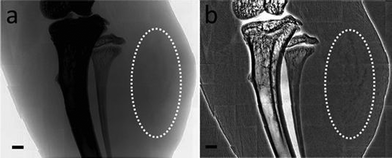

The other important property present only for very small MUA-AuNPs is the extremely high cellular uptake. Fig. 3 shows a >20 fold increase of the amount of internalized Au per cell after culturing with MUA-AuNPs for 24 h, reaching ∼27 pg/cell for 1.4 nm MUA-AuNPs compared to ∼1 pg/cell for 2.2 nm nanoparticles. The fluorescence microscopy images in Fig. 3(b) qualitatively confirm this high uptake. The mechanism of this strong internalization was not yet clarified, but we can exclude the possibility of cross membrane effects and instead hypothesize an endocytosis process. The high uptake is then probably a consequence of stronger interaction of the 1.4 nm AuNPs with cell surfaces. The ability to load large amounts of the AuNPs in cells allows us to use these nanoparticles as cell labeling agents for X-ray imaging in addition to their generic role as contrast agents.26 The very high level uptake, ∼2 × 109 per EMT-6 cell, without affecting the viability and division, we succeeded in imaging the cells in vivo and to follow their growth and evolution into tumors. Fig. 4 shows an example of this imaging strategy: the dark patches in the mouse thigh area are EMT-6 cells inoculated after being loaded with MUA-AuNPs.

(a) and (b) are projection views of photoluminescent MUA-AuNPs loaded in EMT-6 cells that developed tumors; the MUA-AuNPs could also be viewed by X-ray imaging. (b) was processed by background flattening.

Fig. 4 (a) and (b) are projection views of photoluminescent MUA-AuNPs loaded in EMT-6 cells that developed tumors; the MUA-AuNPs could also be viewed by X-ray imaging. (b) was processed by background flattening.